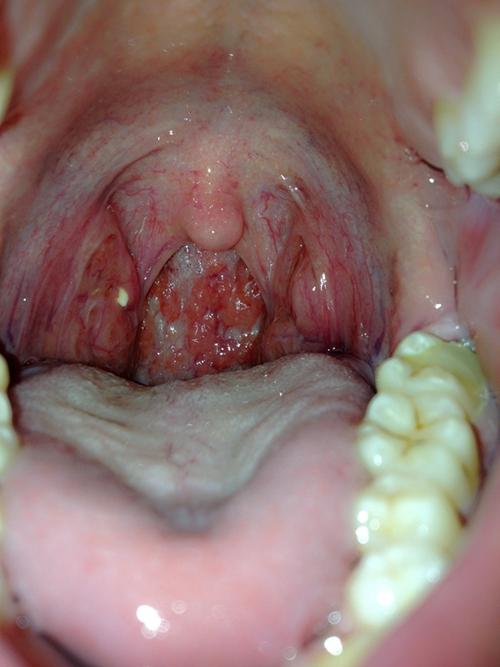

右侧扁桃体菜花状图片

右侧扁桃体菜花状图片,扁桃体一边肿大图片

扁桃体菜花状肿物图片

扁桃体菜花样肿物图片

扁桃体菜花状

扁桃体菜花状图片

扁桃体凹凸不平菜花状

扁桃体一侧菜花状

扁桃体一侧菜花状图片

扁桃体癌菜花状图片